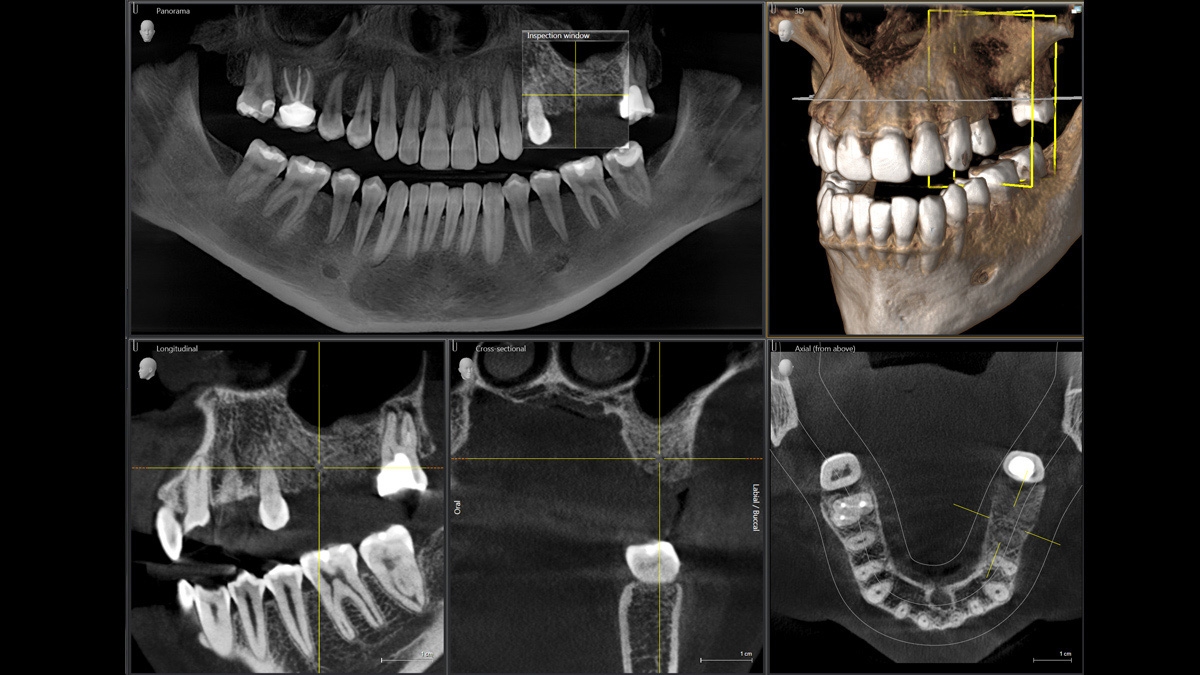

PIA (Patient Positioning & Image Assistant) je 10bodový koncept pro snadné polohování pacienta a rentgenové zobrazování a je především o dvou věcech: vysoké kvalitě snímků a komfortu pro pacienta a obsluhu rentgenu. PIA poskytuje podporu a zajišťuje nástroje pro zhotovení vysoce kvalitních snímků, potřebných pro analýzu léčby. Je zaměřen na ergonomii a komfort pacienta i obsluhy rentgenu. Patentovaný skusový blok automaticky zajistí správné naklonění hlavy, umístění pacienta v okluzní rovině, a spolu s 3bodovou fixací hlavy a pevnými madly pro stabilní polohu pacienta omezuje potřebu nežádoucích korekčních skenů.